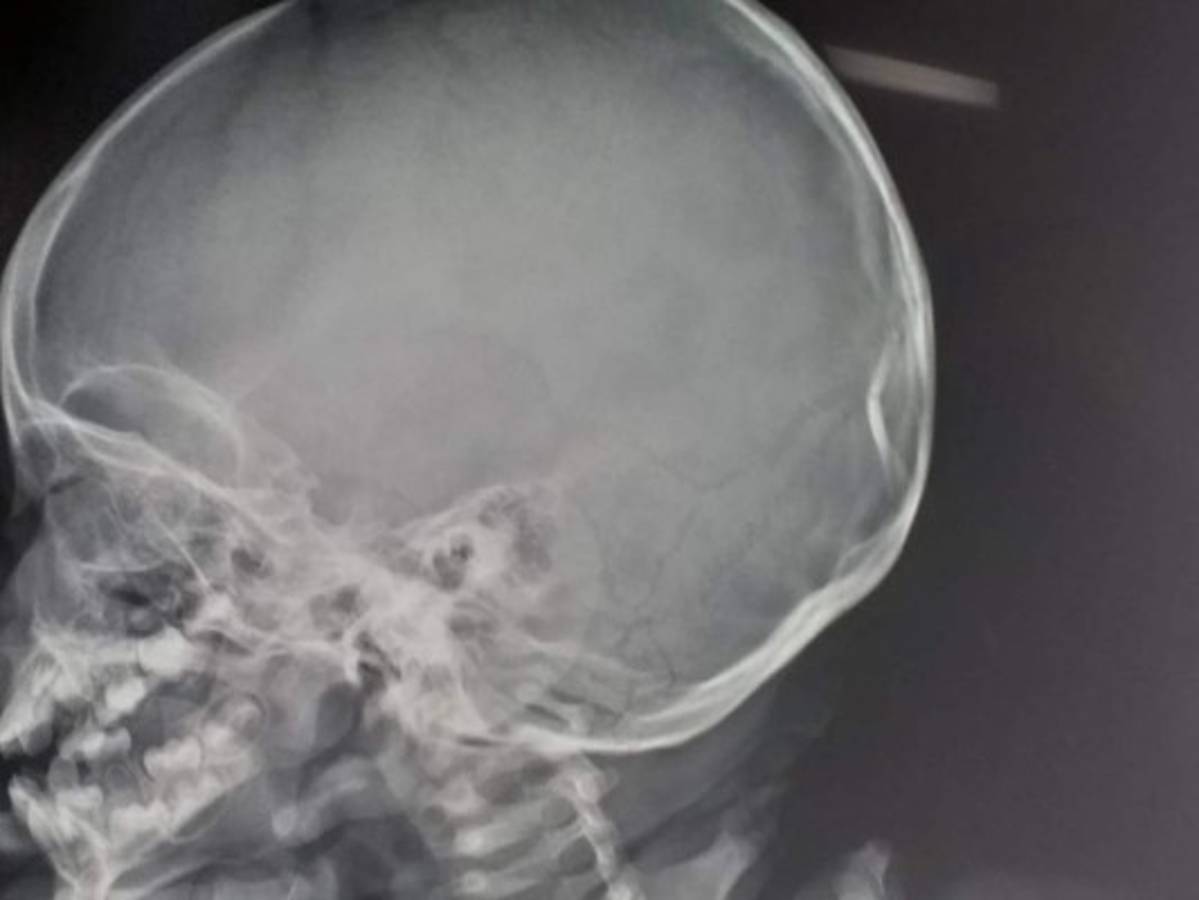

La radiografía muestra la fractura en el cráneo que tiene el menor.

Fractura en el cráneo

'Mi hijo tiene fractura en su cráneo y le harán una tomografía para ver si tiene daño interno', ese fue el mensaje que publicó Nirvana Velásquez horas después de la colisión.

Así quedó el cráneo del niño tras la colisión.